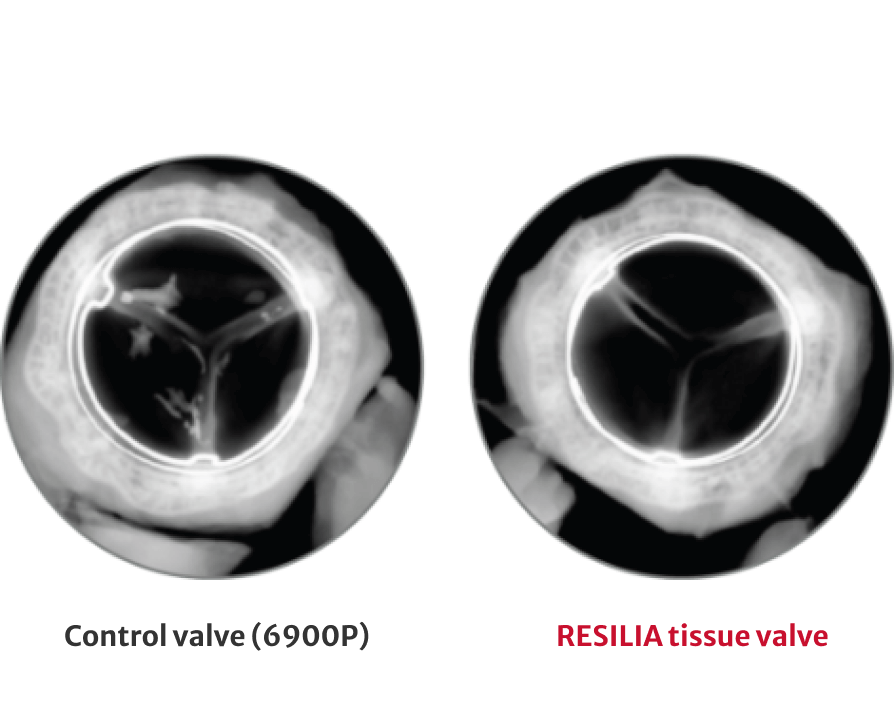

72% less calcium content after 8 months

†RESILIA tissue tested against tissue from commercially available bovine pericardial valves from Edwards in a juvenile sheep model. Flameng, et al. J Thorac Cardiovasc Surg. 2015;149:340-345.